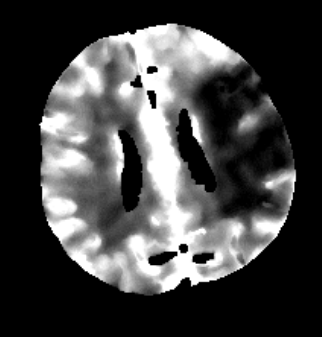

Des Weiteren ist mRay in der Lage eine Verarbeitung von Bildern durchzuführen und so Veränderungen bzw. Anomalien in Geweben zu finden, zu visualisieren und zu quantifizieren. Das Bildverarbeitungsmodul mRay VEOcore kann verwendet werden, um Bilder des Gehirns von Bildgebungsmodalitäten wie CT, Perfusions-CT oder MRT mit diffusionsgewichteter Auswertung (DWI) zu prozessieren. Als Ergebnis werden Kontrastveränderungen über die Zeit als farbige Perfusionskarten angezeigt, dies beinhaltet auch flussbasierte Parameter und Gewebeblutvolumen Berechnungen.

Die Perfusionsanalyse von Aufnahmen des Gehirns ermöglicht die Darstellung und Quantifizierung von minderdurchblutetem Gewebe (Penumbra), nicht-durchblutetem Gewebe (Kerngewebe) und dem Mismatch-Ratio zwischen den beiden Werten. Die berechneten Werte können der Unterstützung bei einer Entscheidungsfindung dienen, die auf der Beurteilung des Ausmaßes der Schädigung von Geweben basiert.